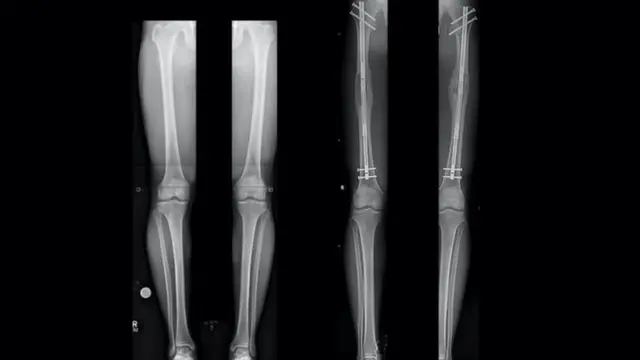

पायाच्या हाडात छेद करून त्याचे दोन तुकडे केले जातात. नंतर शस्त्रक्रियेच्या मदतीने एक रॉड हाडांच्या आत फिक्स केला जातो. या रॉडला दर दिवशी एक मिलीमीटर लांब केलं जातं. हाडं पुन्हा जोडली जाईपर्यंत आणि रुग्णाची इच्छा असेपर्यंत उंची वाढवली जाते.

शस्त्रक्रियेनंतर रुग्णाला अनेक दिवस चालण्याचा प्रयत्न करावा लागतो. या शस्त्रक्रियेदरम्यान नाजूक नसांना इजा होण्याची भीती असते. रक्ताच्या गाठी होऊ शकतात किंवा हाडं पुन्हा जोडली जाऊ शकत नाहीत.